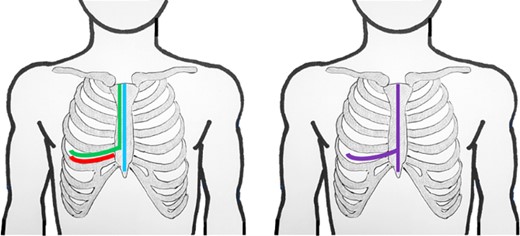

In the anterior mediastinum, common approaches for GMT resection include anterolateral thoracotomy and median sternotomy. For posterior mediastinal GMTs, posterolateral thoracotomy is preferred, and for those situated more deeply in the chest cavity, hemi-clamshell incisions are used [1, 3]. A clamshell incision is the traditional approach when the tumor extends into both hemithoraces [3]. The literature rarely reports on the advantages of a T (⊣) shaped incision, involving a complete sternotomy combined with anterolateral thoracotomy (Fig. 1).

Schematic lines of incision for anterolateral thoracotomy (red); hemiclamshell (green); sternotomy (blue); T-incision (violet).

The advantages of the ⊣ shaped incision are significant. First, it can be adapted from a sternotomy, anterolateral thoracotomy, or a clamshell incision (Fig. 1), providing flexibility when uncertainty initially exists about the need for a ⊣ shaped incision. Second, this approach offers exceptional visibility into one thoracic cavity, and additionally covers the anterior mediastinum and extends, at least partially, into the contralateral thoracic cavity.